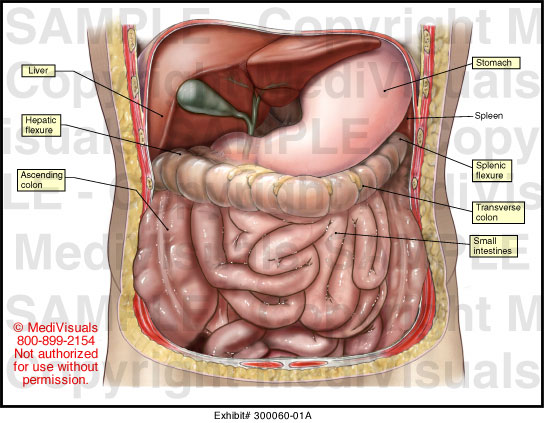

Abdominal Anatomy Medical Illustration Medivisuals

medivisuals1.comanatomy abdominal 01a illustration medical medivisuals1

medivisuals1.comanatomy abdominal 01a illustration medical medivisuals1

www.science-photo.deAbdominal Anatomy - S&A Medical Graphics

www.science-photo.deAbdominal Anatomy - S&A Medical Graphics

samedicalgraphics.comanatomy abdominal medical illustration

samedicalgraphics.comanatomy abdominal medical illustration